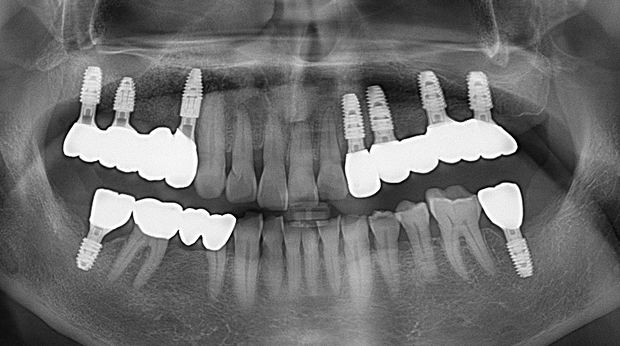

의식하진정법(수면마취)/임플란트

임플란트와 사랑니 발치는 외과적 시술로 잇몸을 절개하는 외과적 시술은

짧으면 짧을 수록 시술 후 붓기와 통증이 최소화됩니다.

치과의사 경력 14년차 구강외과 전문의가 빠르고 안전하게, 아프지 않게 수술해 드립니다.